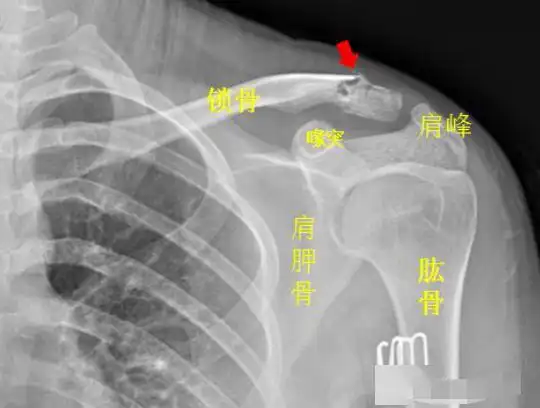

一例锁骨骨折合并肩峰骨折的治疗

锁骨肩峰端骨折钩板固定

左侧锁骨肩峰端见不规则透亮线,骨折处稍移位,左侧锁骨骨折.

肩峰前上缘锁骨外1/4作弯形切口,长约10cm,依次切开各层组织,显露骨折

锁骨肩峰端骨折,第一次使用钩钢板手术

锁骨远端骨折

一例锁骨近端骨折和肩峰骨折,大家看看